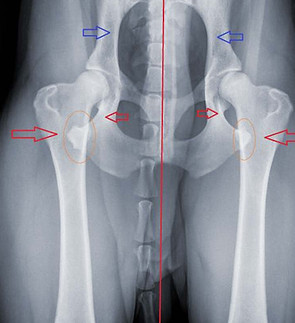

la dysplasie